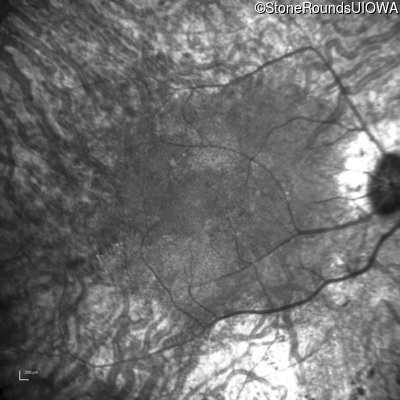

Age at visit: 53 years

This 53 year old woman first noticed night blindness at age 18. More recently she has experienced constriction of her visual fields. She has worn hearing aids since childhood.

Age at visit: 54 years